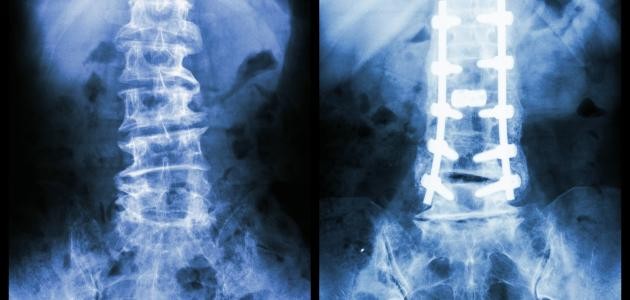

انواع الكسور